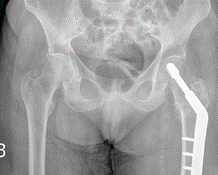

For neck of femur fractures, open reduction and internal fixation are indicated for most physiologically young patients.

Undisplaced fractures are treated with cannulated screws or a sliding hip screw. Arthroplasty is indicated for elderly patients with displaced fractures.

For peri-trochanteric fractures, a dynamic hip screw is done in stable fracture patterns. In unstable fractures, a cephalomedullary nail is indicated. (oblique fractures which would displace with dynamic compression of the hip screw, fractures with subtrochantericextension or medial comminution)